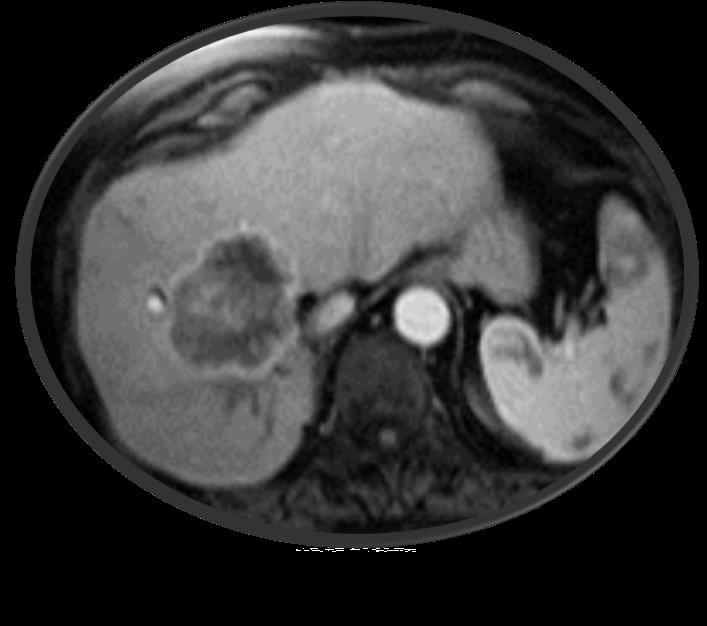

胆管细胞癌介入治疗

胆管细胞癌不是罕见的原发肝脏的肿瘤,预后较差。5年生存率<5%,不治疗的情况下中位生存期3-6个月。治愈性切除<30%,肝外形式生长的更容易切除,外科术后的5年生存率为20-40%。吉西他滨+顺铂的全身化疗中位生存期11.7个月。